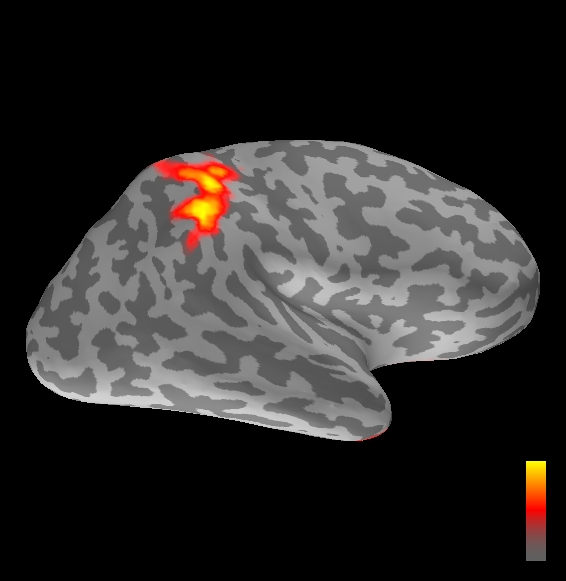

5.2 Results

We applied the ASMC sampler to MEG topographies taken from the above recordings by selecting specific time points according to the previous analysis; the parameter values in the algorithm were the same as those used for the analysis of synthetic data, with the only exception of the noise standard deviation , here estimated from the pre–stimulus interval. In order to validate the results of the ASMC, we also computed source estimates using three other methods: a PF, that approximates the posterior distribution for the current dipoles conditioned on the data up to the selected time point; dSPM, which is based on a distributed source model with an –prior, and consists in normalizing the Tikhonov regularized solution by the noise standard deviation; and sLORETA, which is similar to dSPM but is claimed to have a smaller localization bias. Figure 4 shows the results at , and ms after the stimulus onset. The results are visualized on a computer representation of the brain obtained by “inflating” the cortical surface: gray levels contain the anatomical information, light gray representing gyri and dark gray representing sulci; the activity estimate is coded in color scale, increasing from red to yellow. Importantly, this visualization allows activity in the sulci to be clearly visible; on the other hand, since neighbouring volumes may be moved apart by the inflation process, distinct activity regions are often due to underlying volumetric masses that are very close to each other.

Before describing the results, let us comment on the qualitative difference between the images produced by the ASMC sampler and the PF, on the one hand, and those produced by dSPM and sLORETA, on the other. First of all, we point out that all the quantities shown in the images of Fig. 4 are somehow related to the probability of activation at specific locations. Indeed, for both the ASMC and the PF we plot the approximation of the intensity measure (3.8); for any single grid point, this value can be interpreted as the probability of a dipole being at that location, while it integrates, over a given volume , to the mean number of dipoles within . As for dSPM, the represented quantity is a statistical value that is –distributed under the null–hypothesis of zero activity; as a direct consequence, it also yields a probability of activation, which is however not constrained to be dipolar. Similar considerations apply to sLORETA, although with a different statistical distribution. Importantly, the representation of the results is clearly affected by the setting of the visualization threshold. Owing to the explained differences between the methods, it seems reasonable to use a different value for each method. At the same time, since the plotted quantity is a probability of activation, it seems right to use the same thresholding for different time points. In this connection, the thresholds in Fig. 4 have been chosen by hand following the guidelines just outlined.

Using the same thresholding and parameters at different time points makes the four methods respond differently to the diverse intensities of the different sources. Whenever a stronger source is active, both sLORETA and dSPM will tend to produce widespread estimates, while weaker sources will be represented as small active areas. The behaviour of the ASMC and of the PF is the opposite: a stronger signal will lead to a precise localization of a dipolar source, and then to a focal marginal distribution for the location; a weaker signal will translate to higher uncertainty on the source position, and therefore a more widespread posterior map.

The phenomenon just described is indeed clearly visible in Figure 4. At ms, all the methods correctly identify the rather strong activation in the contra–lateral primary somatosensory cortex: the ASMC and the PF provide very focal maps, while dSPM and sLORETA provide compatible widespread estimates; dSPM also exhibits a more posterior peak which does not fit with the commonly agreed models of the response to median nerve stimulation; this may be due to the formerly described brain inflation.